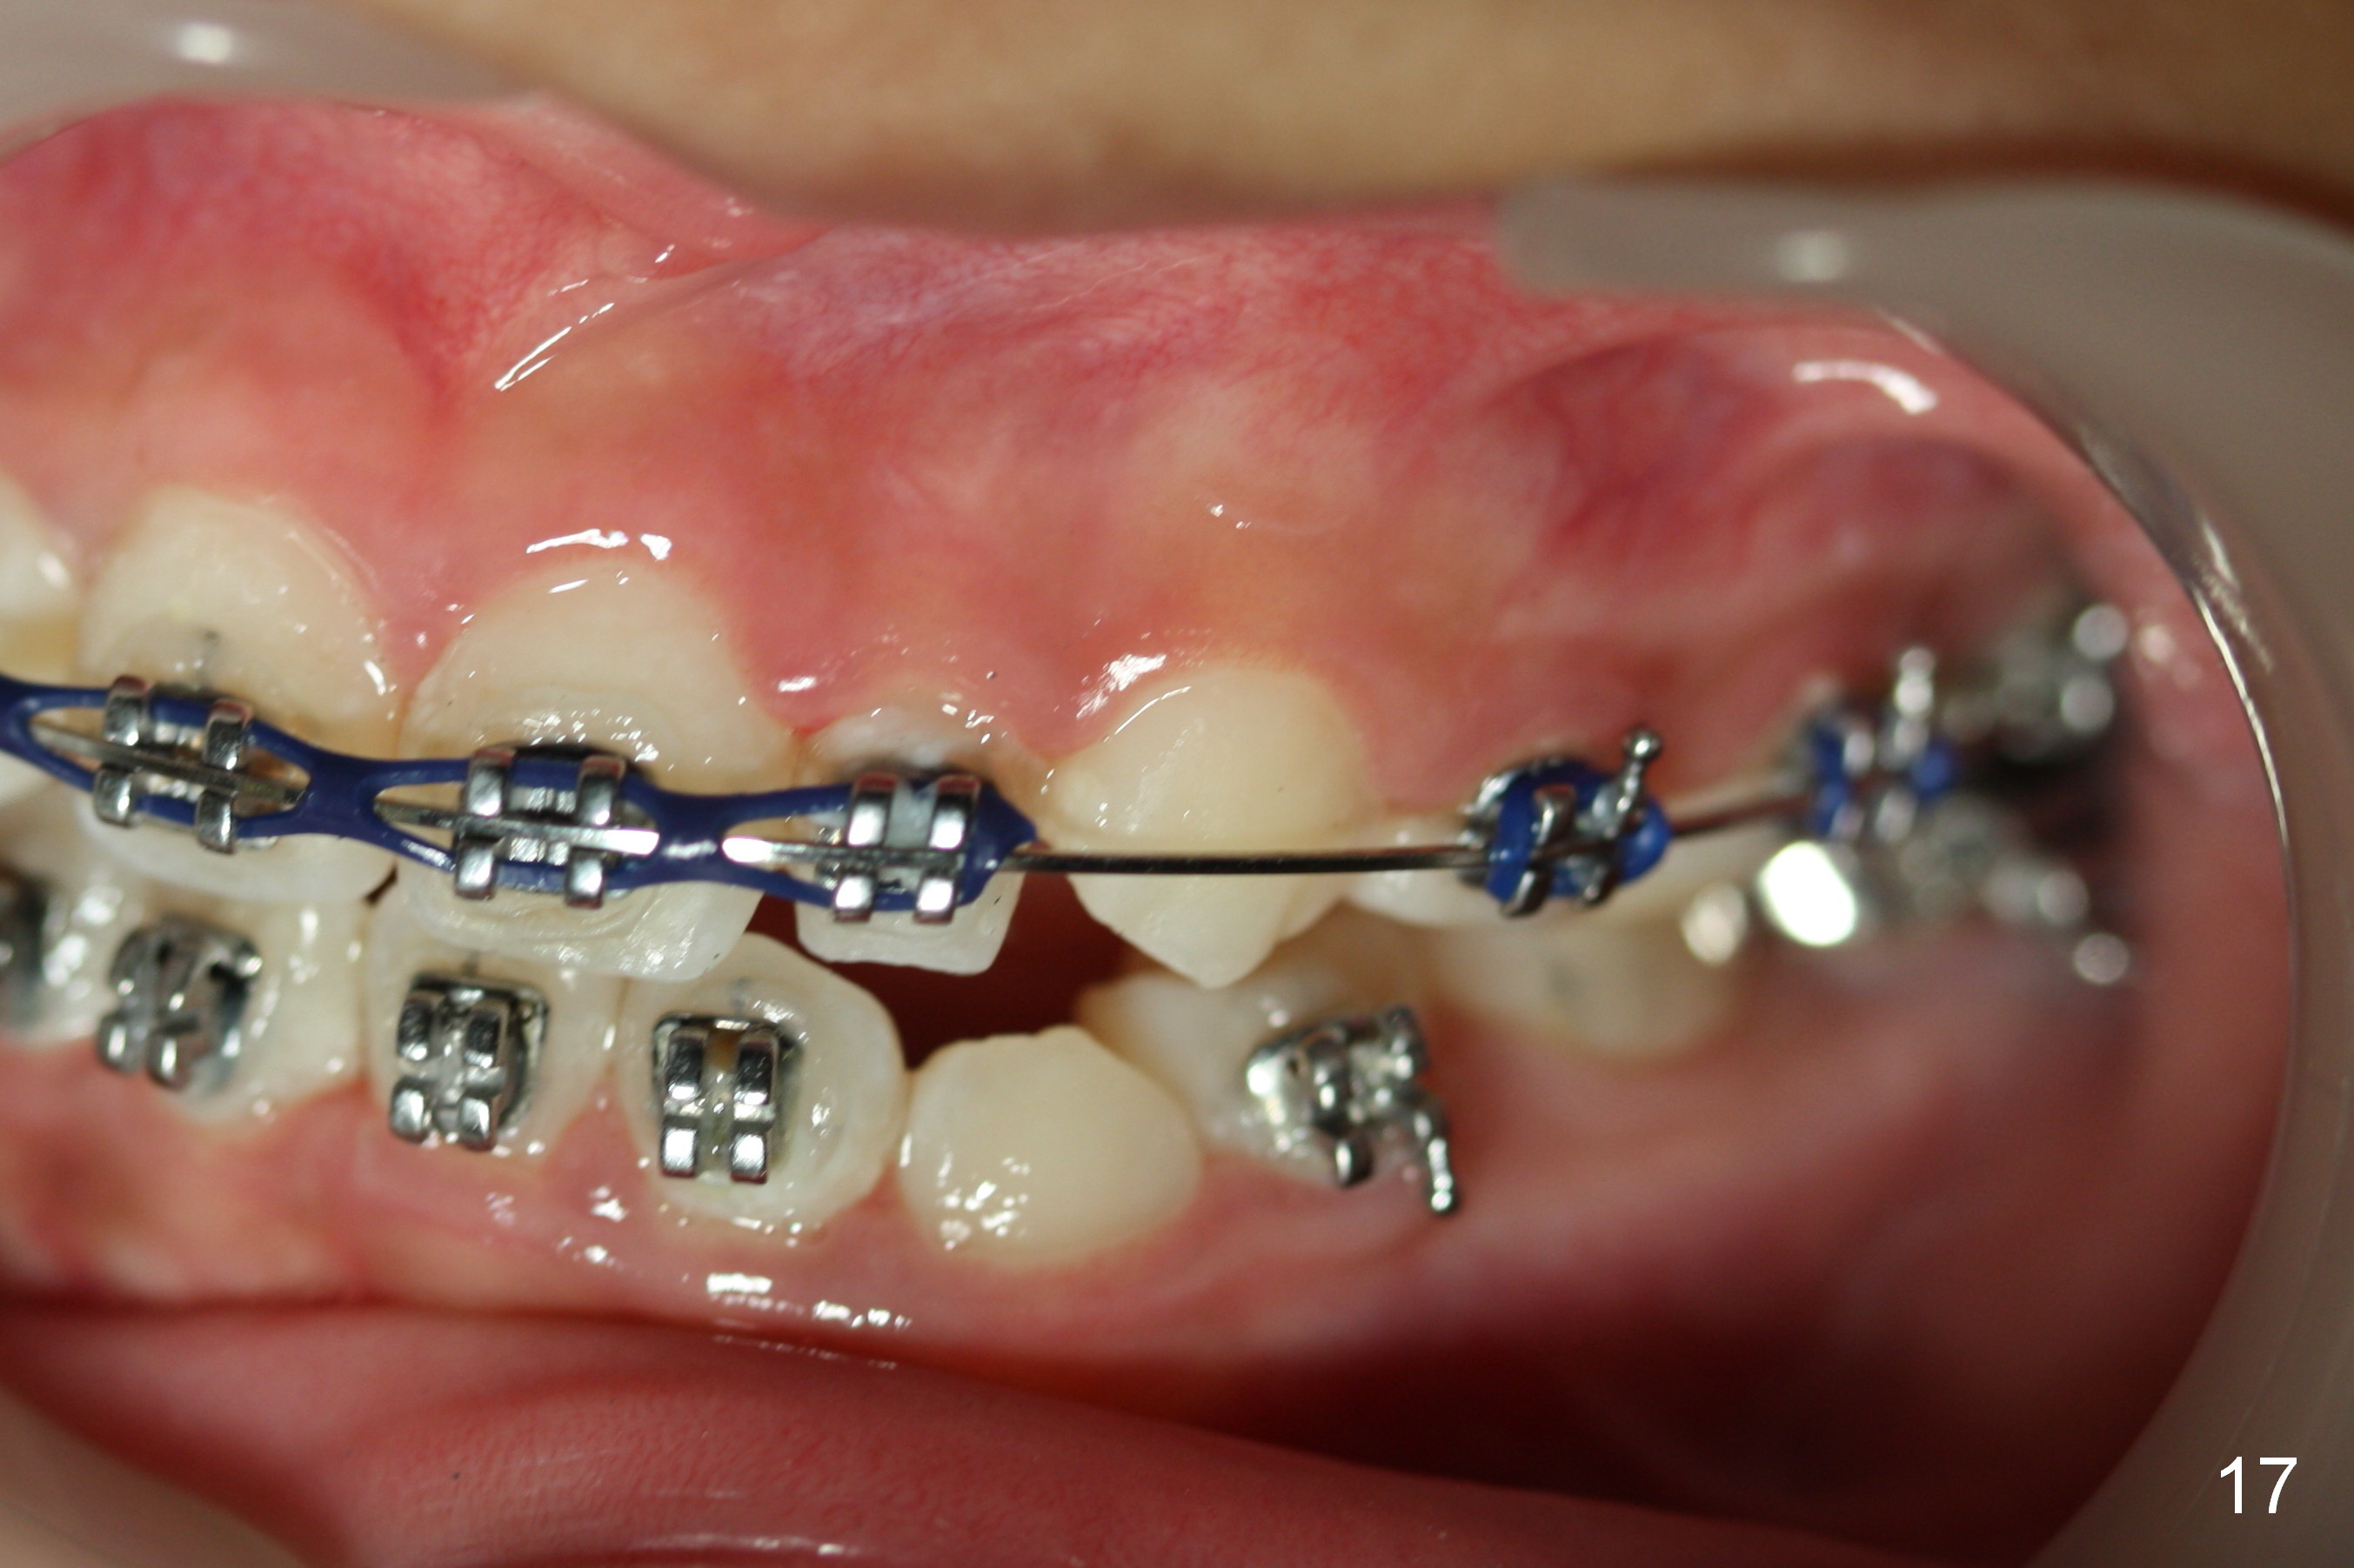

OK Xin, just evaluated the case. If she started with the anterior dental crossbite and you are barely over-corrected right now, I would be very comfortable discontinuing treatment. At her age, there is nothing that can no longer be dealt with beautifully when it is more age appropriate.When anterior cross bite is corrected 19 months post banding, the tooth #10 (microdontia) has tendency of edge-to-edge (Fig.16,17). Power chains are used to create space for #11 to erupt fully before bracketing. In spite of the effort, the peg lateral remains edge-to-edge 23 months post banding (Fig.18,19). The segmental 19x26 braided wire retains as a retainer to prevent #10 from cross bite. The facial profile is more or less normal immediately post debracketing (Fig.20). The anterior occlusion appears to remain basically the same 7 months post debracketing (Fig.21,22). UR3 erupts, while the diastema mesial to UL2 enlarges so that the arch wire appears shorter. UL2,3 appear to be in cross bite 14 months post debracketing, while Es retain at the age of 13 (delayed development, Fig.23).